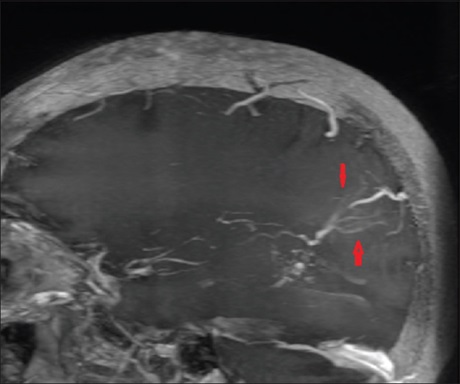

Intraventricular cavernomas are rare lesions with a high propensity for intraventricular hemorrhage and rehemorrhage. Those located in the trigone of the lateral ventricle are even rarer with <20 cases of trigonal cavernomas reported till date. We present a case of a mixed vascular malformation, a trigonal cavernoma with associated developmental venous anomaly (DVA) causing intraventricular hemorrhage.